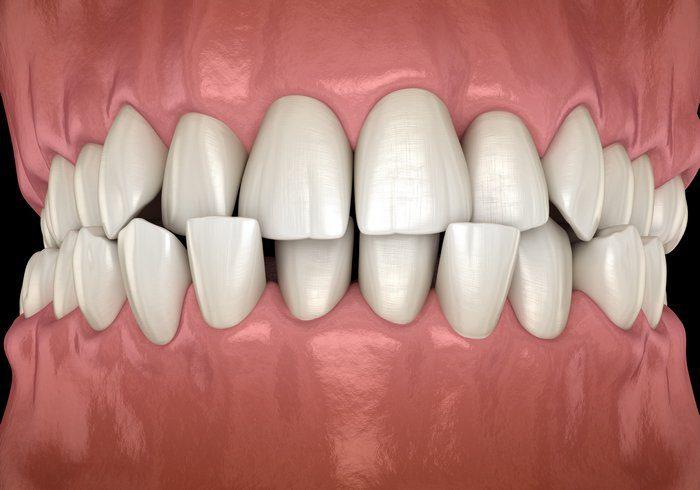

Crooked teeth and jaw misalignment are common dental concerns that can affect both appearance and oral function. Crooked teeth occur when teeth are crowded, rotated, or unevenly spaced, while jaw misalignment involves the improper positioning of the upper and lower jaws. Crooked Teeth Treatment Dubai can influence chewing efficiency, speech, and overall oral health. Understanding the causes and treatment options is essential for maintaining a healthy smile.

Genetics play a significant role in the alignment of teeth. Individuals may inherit jaw sizes that are too small for their teeth, leading to crowding or overlapping. Early loss of baby teeth or permanent teeth can also cause adjacent teeth to shift into empty spaces, resulting in misalignment. Habits during childhood, such as thumb-sucking or prolonged use of a pacifier, may contribute to crooked teeth. Additionally, injuries or trauma to the jaw can affect teeth alignment over time.

Jaw misalignment, also known as malocclusion, can arise from a combination of genetic, developmental, and environmental factors. A mismatch in jaw size between the upper and lower jaw is a common contributor. Uneven growth during childhood or adolescence can result in overbite, underbite, or crossbite conditions. Trauma to the jaw, such as fractures or dislocations, may also cause misalignment. Functional habits, including teeth grinding and clenching, can worsen jaw positioning if left unaddressed.